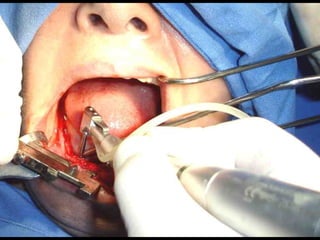

Segundo tiempo quirúrgico para aplicar la estructura.

Estructura en íntimo contacto con la superficie ósea, quedando los postes

fuera de la fibromucosa gingival..

Sutura de colgajos que cubren la estructura, dejando los postes bien visibles.

Colocación de la prótesis dentaria.

Segundo tiempo quirúrgico:

Estructura implantada por debajo del periostio:

• Los implantes subperiósticos son parte de la historia de la

Odontología, sin embargo en su momento fueron una buena

solución para casos protésicos difíciles.